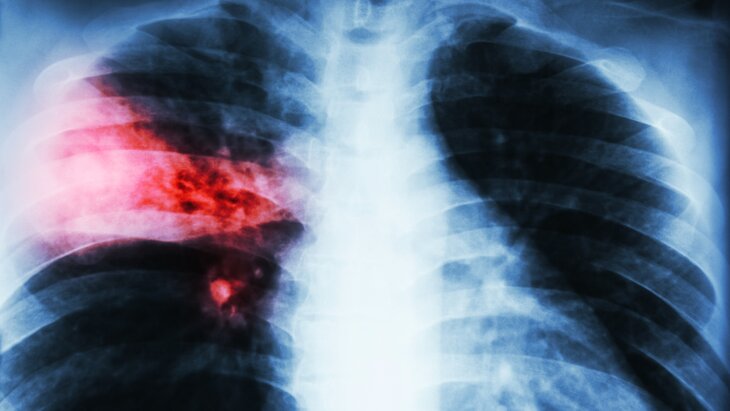

Продолжительный кашель, боли в груди, охриплость, потеря аппетита и снижение веса, одышка, слабость и постоянные бронхиты могут указывать на развитие рака легких. О том, какие факторы повышают вероятность его появления, врач-онколог высшей категории, торакальный онколог и хирург Замир Абдуллин рассказал в беседе с UfaNovosti.ru.